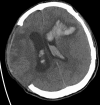

Traumatic intracranial pseudoaneurysms are a rare but severe complication following arterial injury. Pseudoaneurysm formation can occur secondary to blunt or penetrating trauma or iatrogenic injury. We report a case of traumatic pseudoaneurysm secondary to placement of an intracranial pressure (ICP) monitor. A 27-year-old man was involved in a motorcycle accident resulting in multiple intracranial hemorrhages. The patient underwent craniectomy and placement of an ICP monitor. 17 days later he developed dilation of his left pupil, with imaging demonstrating a new hemorrhage in the vicinity of the previous ICP monitor. A cerebral angiogram confirmed a left-sided distal M4 pseudoaneurysm which was treated by n-butyl cyanoacrylate embolization. Intracranial pseudoaneurysm formation following neurosurgical procedures is uncommon. Delayed intracranial hemorrhage in a region of prior intracranial manipulation, even following a procedure as 'routine' as placement of an ICP monitor, should raise the suspicion for this rare but potentially lethal complication.